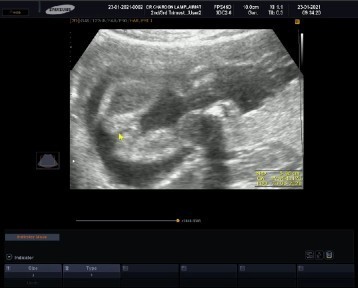

ซาวด์ตอน22สัปดาห์ จะเป็นเพศหญิงหรือเพศชาย แม่ๆช่วยดูหน่อยค่ะ ท้องแรก #ขอบคุณล่วงหน้านะคะ ❤️